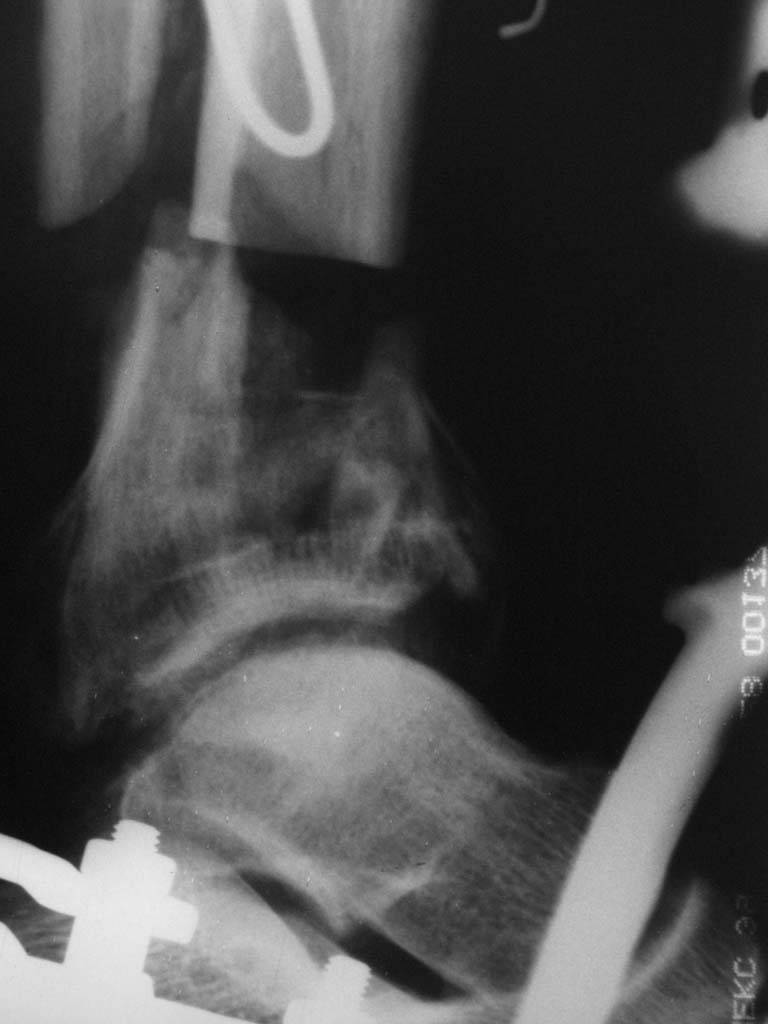

Ерсин, мы тоже имеем опыт такой фиксации. Подобную операцию за последние 3 года мы сделали трем пациентам. Снимки одного из них я прилагаю.

К сожалению, ни в одном из этих 3-х случаев мы не получили удовлетворяющего нас результата. Очень трудно провести штифт, введенный антеградно ровно по центру таранной кости. Отсутствие подвижности между диафизом и дистальным отломком большеберцовой кости (после фиксации в аппарате в течение 1-2 мес) очень усложняет проведение штифта в центр блока таранной кости. Поэтому мы от этого пока отказались, и проводим штифт через пятку. При данном варианте фиксации подобных проблем не возникало ни разу.